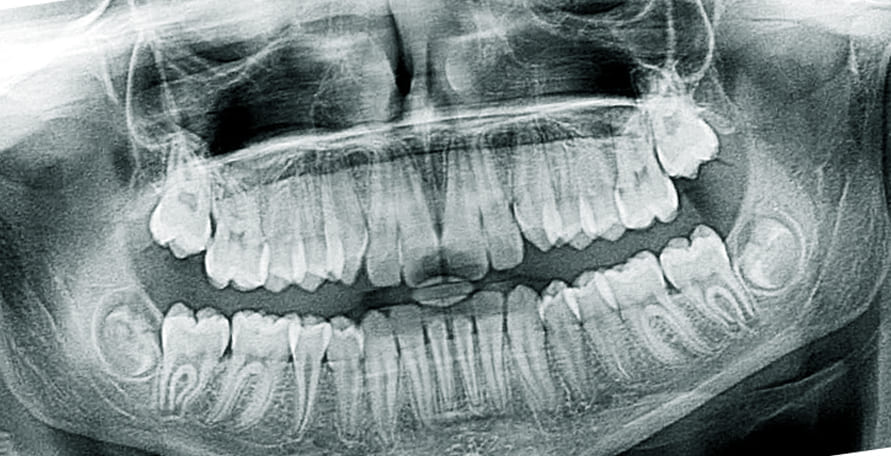

최근에는 3차원 CT스캔을 이용해 자신의 치아 상태에 최적화된 임플란트를 만들 수 있을정도로 꼼꼼한 진단과 세심할 시술이 가능하니 적응할 수 있을까 라는 걱정은 하지 않아도 됩니다.